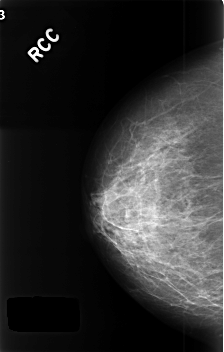

C_0405_1.RIGHT_CC

RIGHT_CC LINES 4568 PIXELS_PER_LINE 2912 BITS_PER_PIXEL 12 RESOLUTION 50 NON_OVERLAY